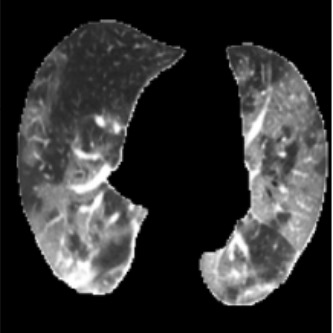

In the field of medical imaging, particularly in tasks related to early disease detection and prognosis, understanding the reasoning behind AI model predictions is imperative for assessing their reliability. Conventional explanation methods encounter challenges in identifying decisive features in medical image classifications, especially when discriminative features are subtle or not immediately evident. To address this limitation, we propose an agent model capable of generating counterfactual images that prompt different decisions when plugged into a black box model. By employing this agent model, we can uncover influential image patterns that impact the black model's final predictions. Through our methodology, we efficiently identify features that influence decisions of the deep black box. We validated our approach in the rigorous domain of medical prognosis tasks, showcasing its efficacy and potential to enhance the reliability of deep learning models in medical image classification compared to existing interpretation methods. The code will be publicly available at https://github.com/ayanglab/DiffExplainer.